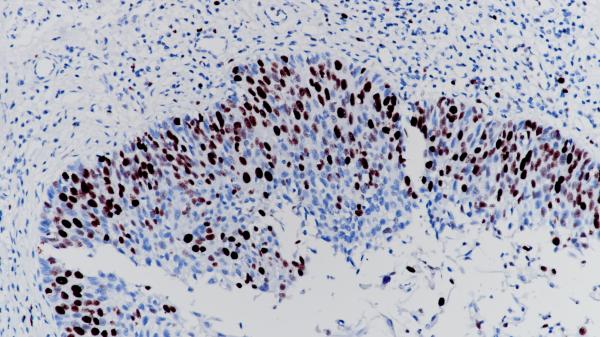

Ki-67

BP6045

BP6132